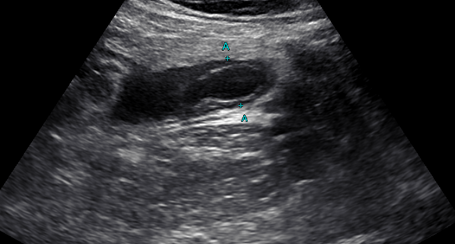

• 超音波検査